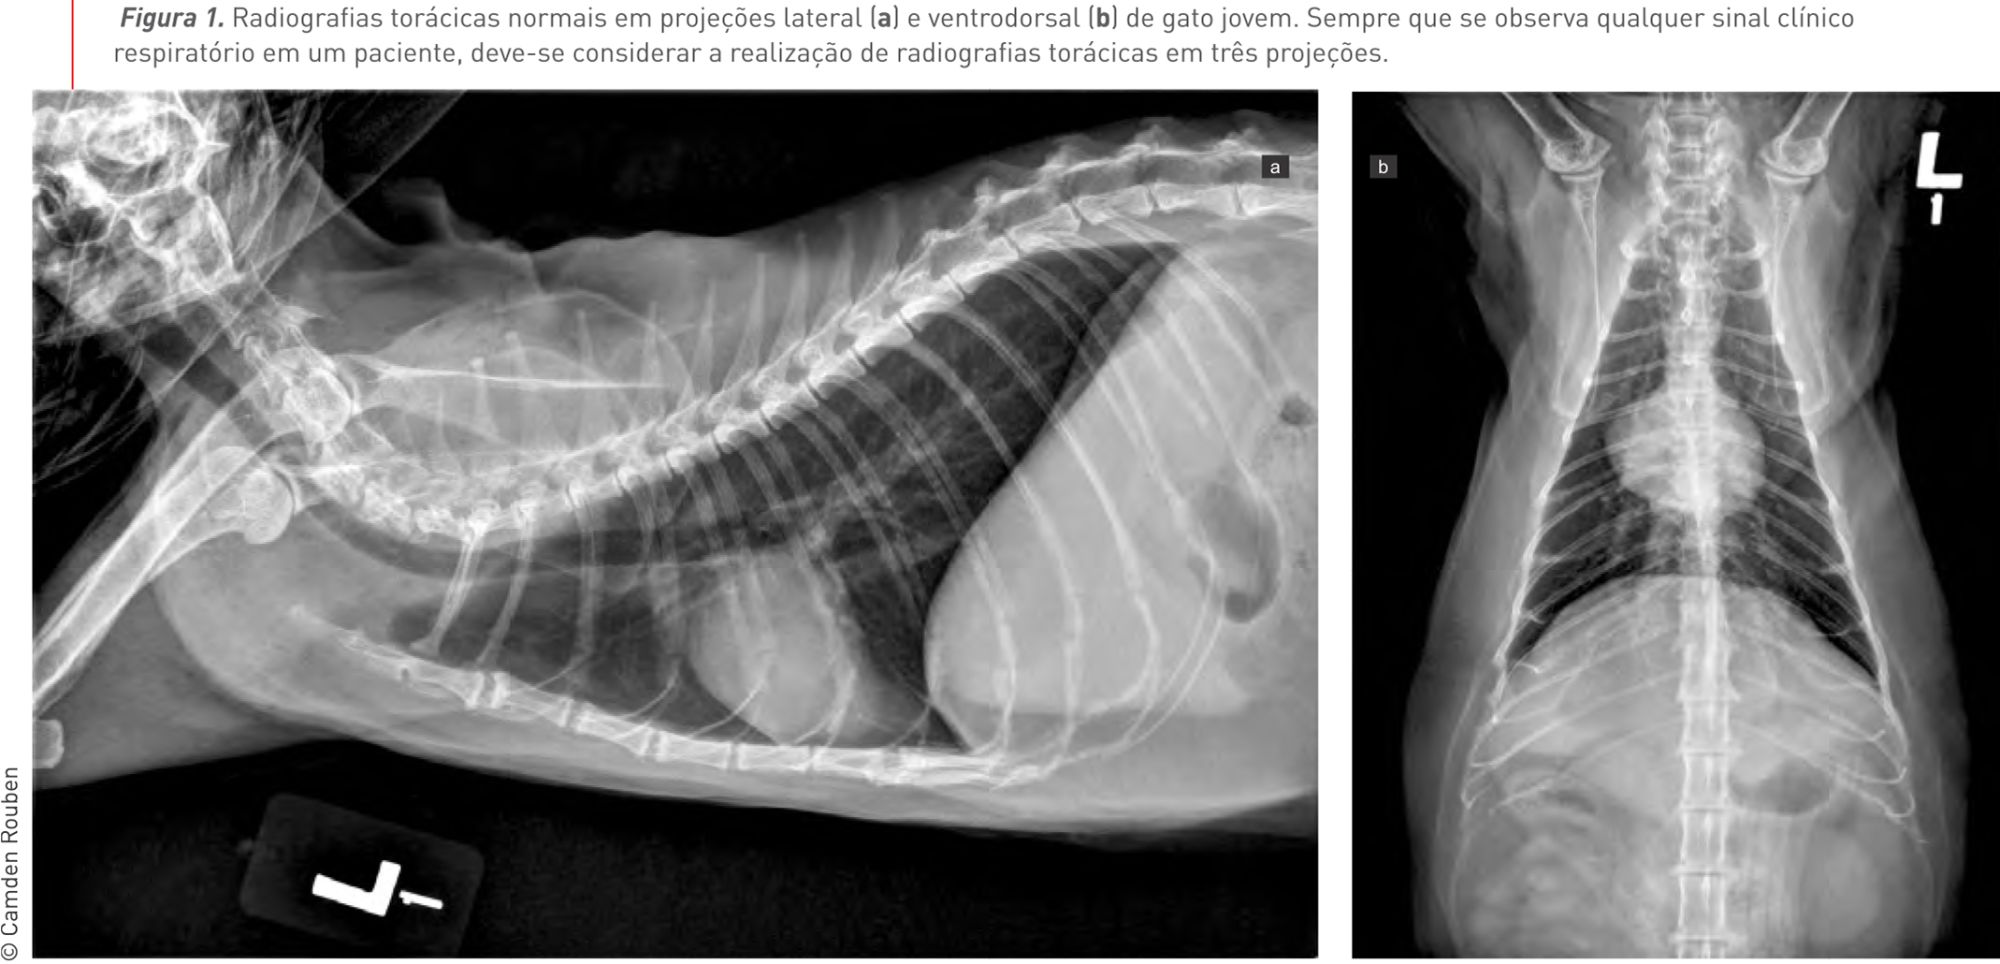

A frequência e o esforço respiratórios devem ser avaliados quando o paciente se encontra calmo e tranquilo. Infelizmente, a auscultação pulmonar não é um método de diagnóstico muito sensível para edema pulmonar ou efusão pleural em gatos. Portanto, sempre que houver qualquer sinal clínico atribuído ao sistema respiratório em seu paciente, deve-se considerar a obtenção de radiografias torácicas em três projeções (duas em projeção lateral [laterolaterais] e uma em projeção ventrodorsal) (Figuras 1-3). O abdome deve ser delicadamente palpado para detectar a presença de organomegalia ou ascite, o que sugere uma insuficiência cardíaca direita. Da mesma forma, a congestão venosa generalizada e/ou o pulso jugular são indicativos de cardiopatia do lado direito. A Tabela 1 lista os defeitos cardíacos congênitos mais comuns em gatos.

Figura 1. Radiografias torácicas normais em projeções lateral (a) e ventrodorsal